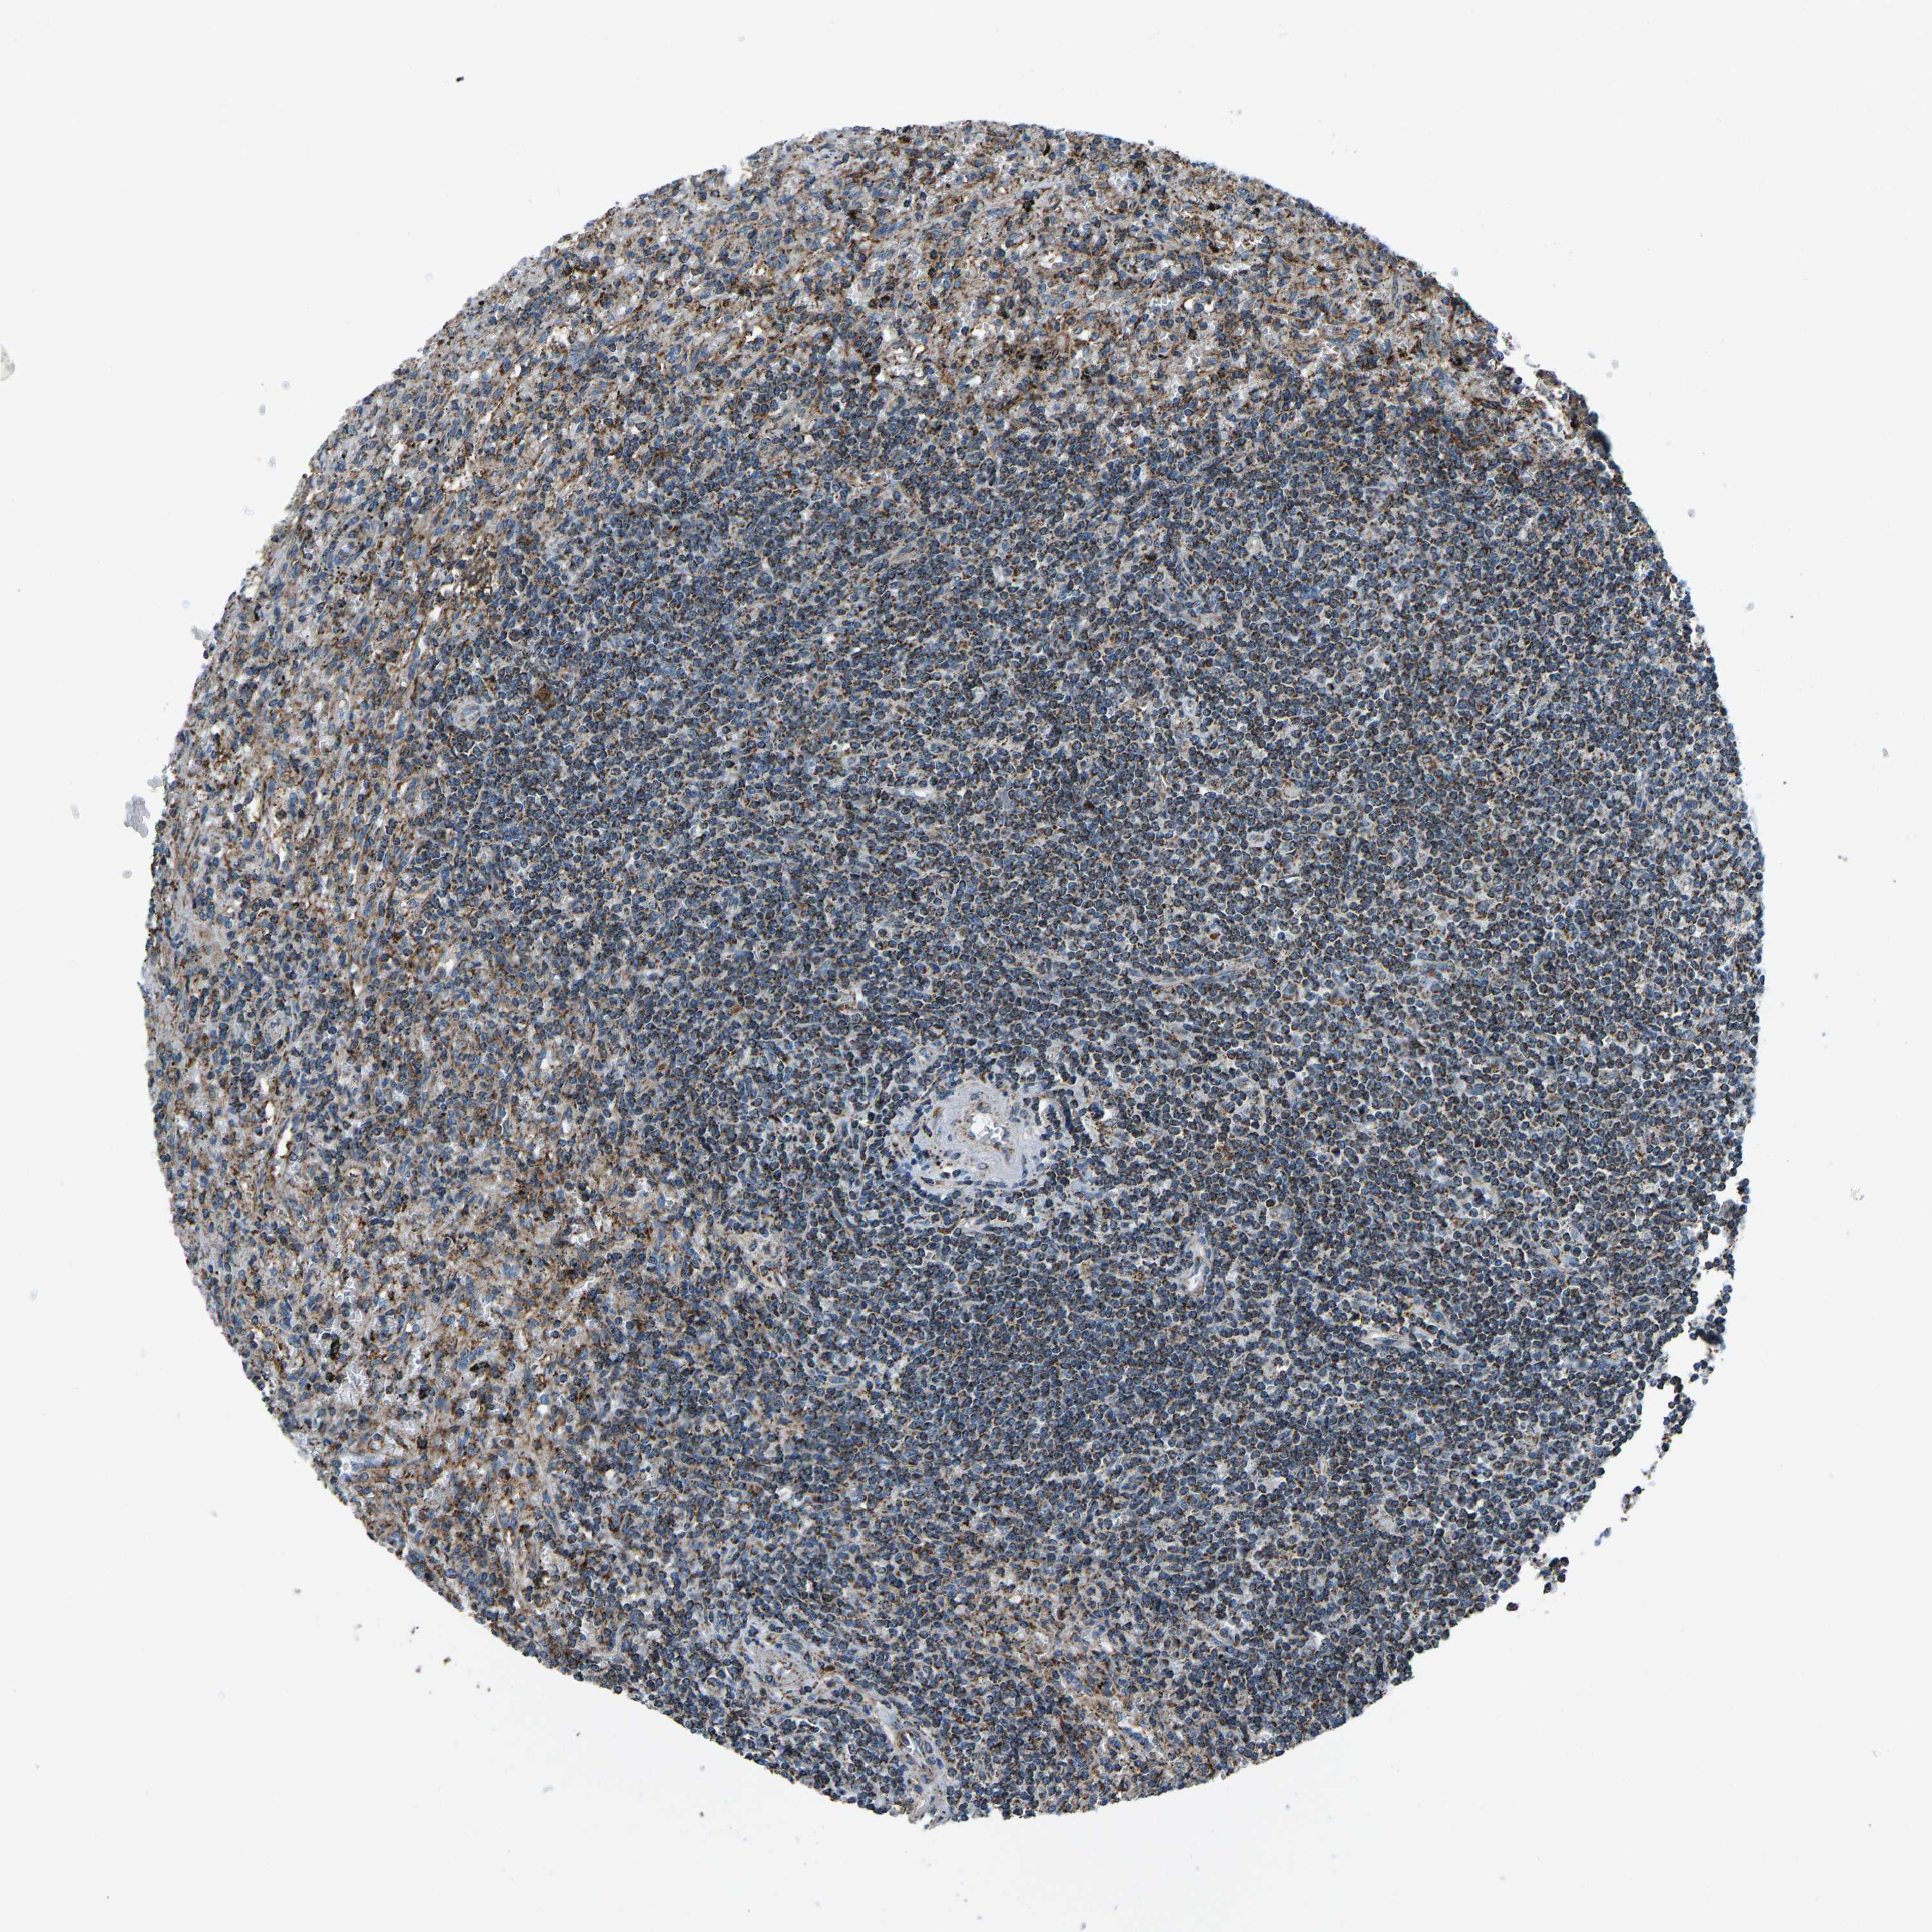

CANCER LYMPHOMA Show tissue menu

LYMPHOMA - Protein expressioni

A mouse-over function shows sample information and annotation data. Click on an image to view it in a full screen mode. Samples can be filtered based on level of antibody staining by selecting one or several of the following categories: high, medium, low and not detected. The assay and annotation is described here.

Each image is clickable and will lead to virtual microscopy that enables deeper exploration of all samples and also displays staining intensity scores, fraction scores and subcellular localization as well as patient and tissue information for each sample.

Antibody HPA021768

Hodgkin's disease, NOS

Malignant lymphoma, non-Hodgkin's type, High grade

Malignant lymphoma, non-Hodgkin's type, Low grade